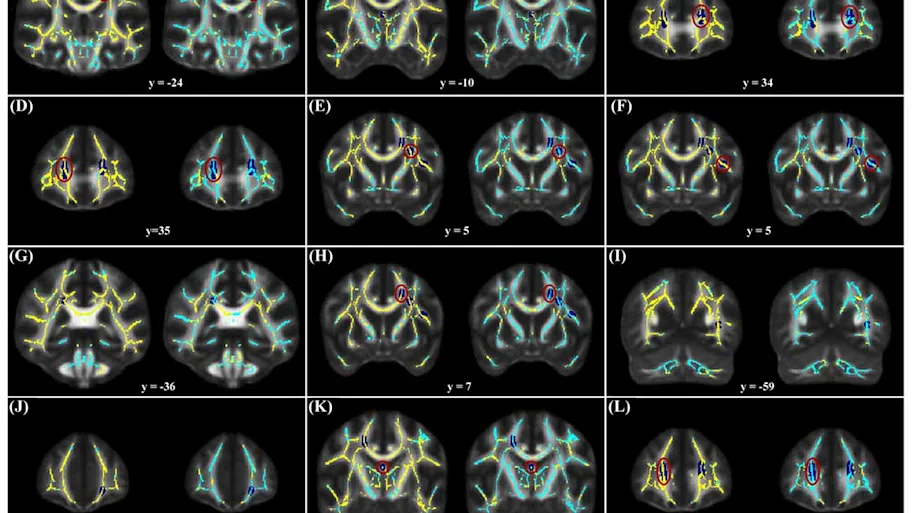

The studies show that playing video games can change how our brains perform, and even their structure. For example, playing video games affects our attention, and some studies found that gamers show improvements in several types of attention, such as sustained attention or selective attention. The brain regions involved in attention are also more efficient in gamers and require less activation to sustain attention on demanding tasks.

There is also evidence that video games can increase the size and efficiency of brain regions related to visuospatial skills. For example, the right hippocampus was enlarged in both long-term gamers and volunteers following a video game training program.

Video games can also be addictive, and this kind of addiction is called “Internet gaming disorder”. Researchers have found functional and structural changes in the neural reward system in gaming addicts, in part by exposing them to gaming cues that cause cravings and monitoring their neural responses. These neural changes are basically the same as those seen in other addictive disorders.